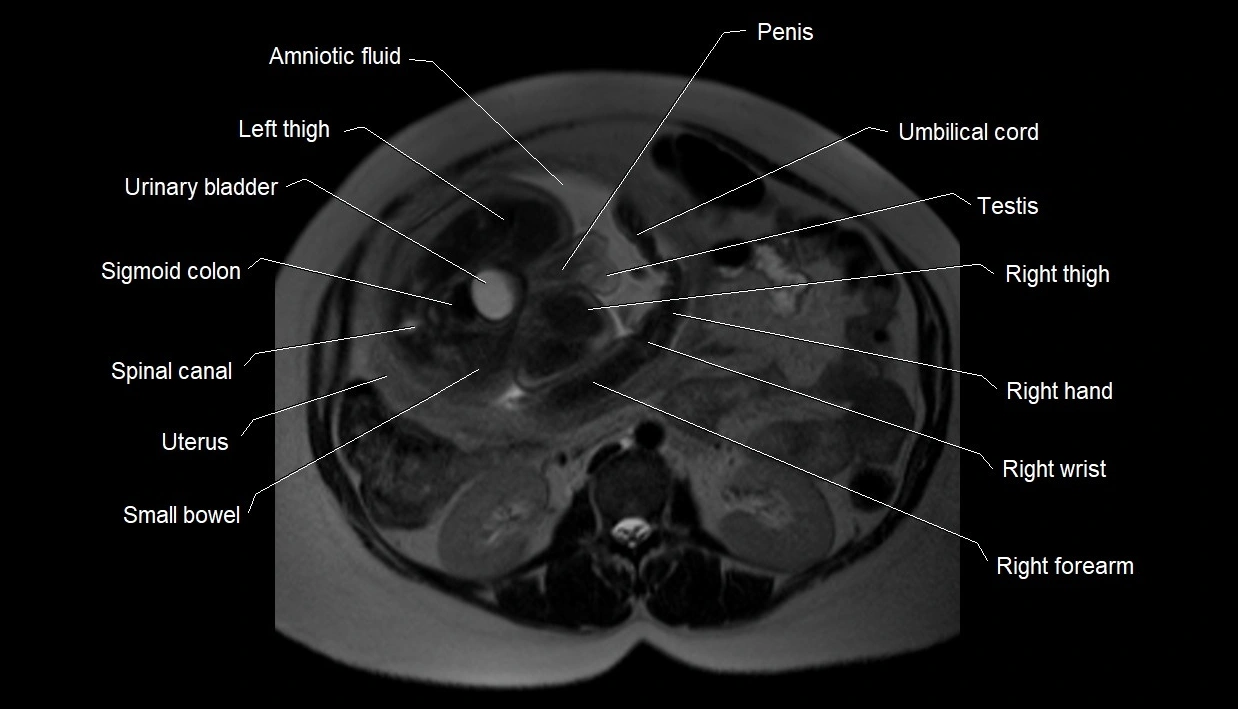

MRI Appearance

T2 HASTE (T2 GRE):

• Amniotic fluid shows very bright hyperintense signal

• Provides natural contrast against fetus and placenta

• Small particles (vernix) may appear as scattered hypointense foci within bright fluid